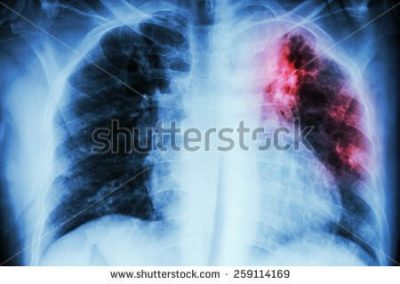

Tüberküloz veya Verem; Mycobacterium türlerinin neden olduğu, genellikle Mycobacterium tuberculosis'in neden olduğu uzun seyirli ve ...